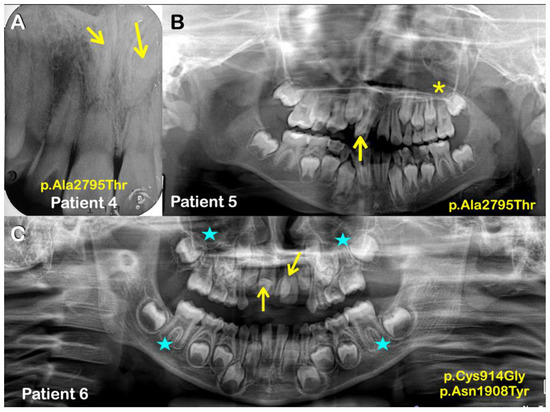

| Families | Patients | Phenotypes | APC Variants NM_000038.6; NP_000029.2 | Prediction/Ranking |

|---|---|---|---|---|

| 4 | Normal mother | No variants | MutationTaster: Disease causing Prob = 0.999223891277048 Polyphen-2: Probably damaging; score = 0.936 SIFT: Tolerated; score = 0.068 CADD-PHRED score = 22.2 DANN score = 0.9909 | |

| 4 (Male) | Mesiodens (Double; unerupted & inverted) | c.8383G>A p.Ala2795Thr chr5-112179674-G-A rs369264968 MAF:0.00004400 | ||

| 5 (Male) | Mesiodens (Double; both were erupted) | |||

| Normal sister | No variants | |||

| 5 | 6 (Male) | Mesiodens (Double; unerupted) One is inverted, the other had normal orientation | Variant 1 c.2740T>G p.Cys914Gly chr5-112174031-T-G rs1554084426 Not reported in gnomAD Variant 2 c.5722A>T p.Asn1908Tyr chr5-112177013-A-T No rs number Not reported in gnomAD | Variant 1 MutationTaster: Disease causing Prob = 0.99929839701033 Polyphen-2: Benign score = 0.055 SIFT: Tolerated; score = 0.127 CADD-PHRED score = 21.5 DANN score = 0.8956 Variant 2 MutationTaster: Polymorphism Prob = 0.999999988244843 Polyphen-2: Benign score = 0.214 SIFT: Damaging; score = 0.046 CADD-PHRED score = 17.19 DANN score = 0.9609 |